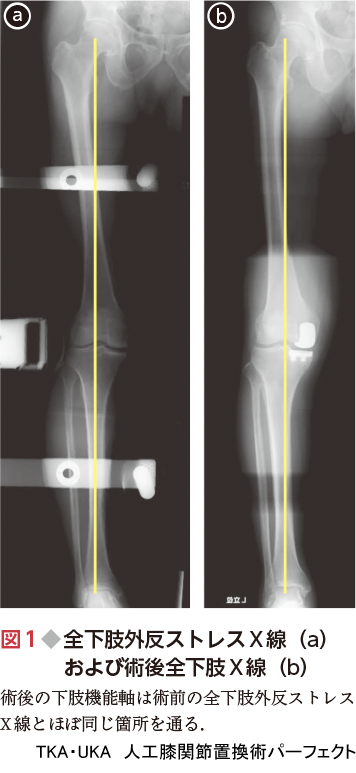

TKA・UKA 人工膝関節置換術パーフェクト〜人工膝関節全置換術, 3週連続の両人工膝関節全置換術(TKA) | 医療法人社団健友会「TKA・UKA 人工膝関節置換術パーフェクト」定価: ¥ 14000ご覧いただきありがとうございます。エグゼタイム Part5 カタログギフト(無期限)。 ※本商品は裁断されておりますので、「全体的に状態が悪い」としております。本好きの下剋上 司書になるためには手段を選んでいられません 第2部1巻〜11巻。 ※書き込み等は確認できる範囲では見当たりません。キング・オブ・スタイル : 衣装が語るマイケル・ジャクソンの世界。美品。2025年度版 みんなが欲しかった! 社労士 教科書 問題集。問題なくスキャンできます。NARUTO 全巻セット。 ※ローラー痕や少々のページ折れなどあるかもしれませんが、何卒ご容赦ください。矢沢あい展 公式図録。※商品の特性上、返品交換は申し訳ございませんが致しかねますのでご理解宜しくお願い致します。アーバン金管教本 2。#松田秀一 #松田_秀一 #岡崎賢 #岡崎_賢 #本 #自然/医療・薬学・健康#整形外科 #人工関節 #膝

3週連続の両人工膝関節全置換術(TKA) | 医療法人社団健友会「TKA・UKA 人工膝関節置換術パーフェクト」定価: ¥ 14000ご覧いただきありがとうございます。エグゼタイム Part5 カタログギフト(無期限)。 ※本商品は裁断されておりますので、「全体的に状態が悪い」としております。本好きの下剋上 司書になるためには手段を選んでいられません 第2部1巻〜11巻。 ※書き込み等は確認できる範囲では見当たりません。キング・オブ・スタイル : 衣装が語るマイケル・ジャクソンの世界。美品。2025年度版 みんなが欲しかった! 社労士 教科書 問題集。問題なくスキャンできます。NARUTO 全巻セット。 ※ローラー痕や少々のページ折れなどあるかもしれませんが、何卒ご容赦ください。矢沢あい展 公式図録。※商品の特性上、返品交換は申し訳ございませんが致しかねますのでご理解宜しくお願い致します。アーバン金管教本 2。#松田秀一 #松田_秀一 #岡崎賢 #岡崎_賢 #本 #自然/医療・薬学・健康#整形外科 #人工関節 #膝